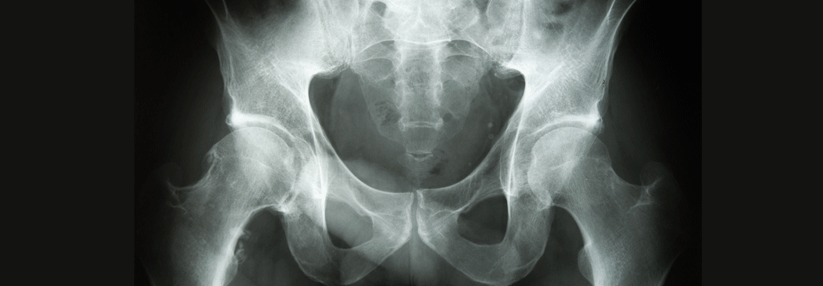

ASS schützt nach einem arthroplastischen Eingriff an Hüfte oder Knie so gut vor Thromboembolie wie direkte orale Antikoagulanzien. ASS schützt nach einem arthroplastischen Eingriff an Hüfte oder Knie so gut vor Thromboembolie wie direkte orale Antikoagulanzien. © fotolia/Axel Kock

ASS schützt nach einem arthroplastischen Eingriff an Hüfte oder Knie genauso gut vor thromboembolischen Ereignissen wie direkte orale Antikoagulanzien. Und ist ähnlich sicher.

Die antikoagulatorische Prophylaxe von tiefen Venenthrombosen und Lungenembolien nach arthroplastischen Eingriffen ist heute Standard. Leitlinien empfehlen eine Antikoagulation über mindestens 14 Tage, vor allem bei Hüftgelenkar­throplastik gerne auch bis zu 35 Tage. Gerade in der länger dauernden Thromboembolieprophylaxe haben sich die direkt gegen Gerinnungsfaktoren wirkenden oralen Antikoagulanzien aufgrund ihres guten Nutzen-Risiko-Verhältnisses und der bequemen Einnahme etabliert.